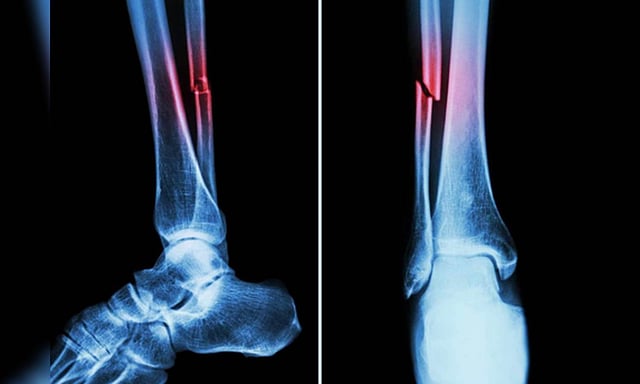

Representative Image (IANS)

The automated system analyses vertebral fracture assessment (VFA) images to detect abdominal aortic calcification (AAC) -- a key marker linked to heart attacks, strokes, and falls.

Traditionally, assessing AAC requires around five to six minutes per image by a trained expert. The new algorithm slashes that time to under a minute for thousands of images, making large-scale screening far more efficient, it said.

Further research by ECU's Marc Sim revealed that AAC is not only a cardiovascular risk indicator but also a strong predictor of falls and fractures. In fact, AAC outperformed traditional fall risk factors like bone mineral density and past fall history.

"The higher the calcification in your arteries, the higher the risk of falls and fractures," Sim said, adding clinicians typically overlook vascular health in fall assessments, and this algorithm changes that.